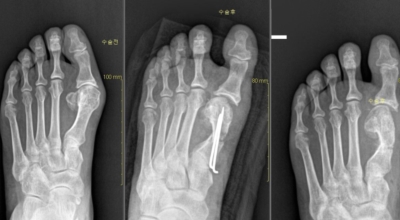

보존적 요법은 변형이 심하지 않은 경우 먼저 고려되는 치료법입니다. 굽이 높고 신발코가 뾰족한 신발을 피하고, 편한 신발을 착용해 발의 압박을 최소화시켜요. 신발 안에 중족골 패드나 발가락교정기 등 교정 도구를 착용해 압력을 재분배해서 증상을 완화시켜요. 그리고 보존적인 요법으로 증상이 완화되지 않거나 통증이 무척 심한 경우 수술이 고려되어요.

초기 단계에서는 건막류(두꺼운 혹)를 절제하는 건막류절제술을 시행해요. 돌출된 건막류를 절제해서 각을 교정하고 짧아진 근육 또는 연부조직을 늘려주는 비교적 간단한 수술입니다. 다른 발가락의 변형이 동반되거나 뼈의 과잉성장이 심하면 뼈를 깎고 방향을 돌린 뒤 발가락이 똑바로 펴지도록 철사로 고정시키는 등 교정절골술을 시행해요. 양 발이 모두 변형된 경우 대부분이 한 번에 한쪽만 수술해요.